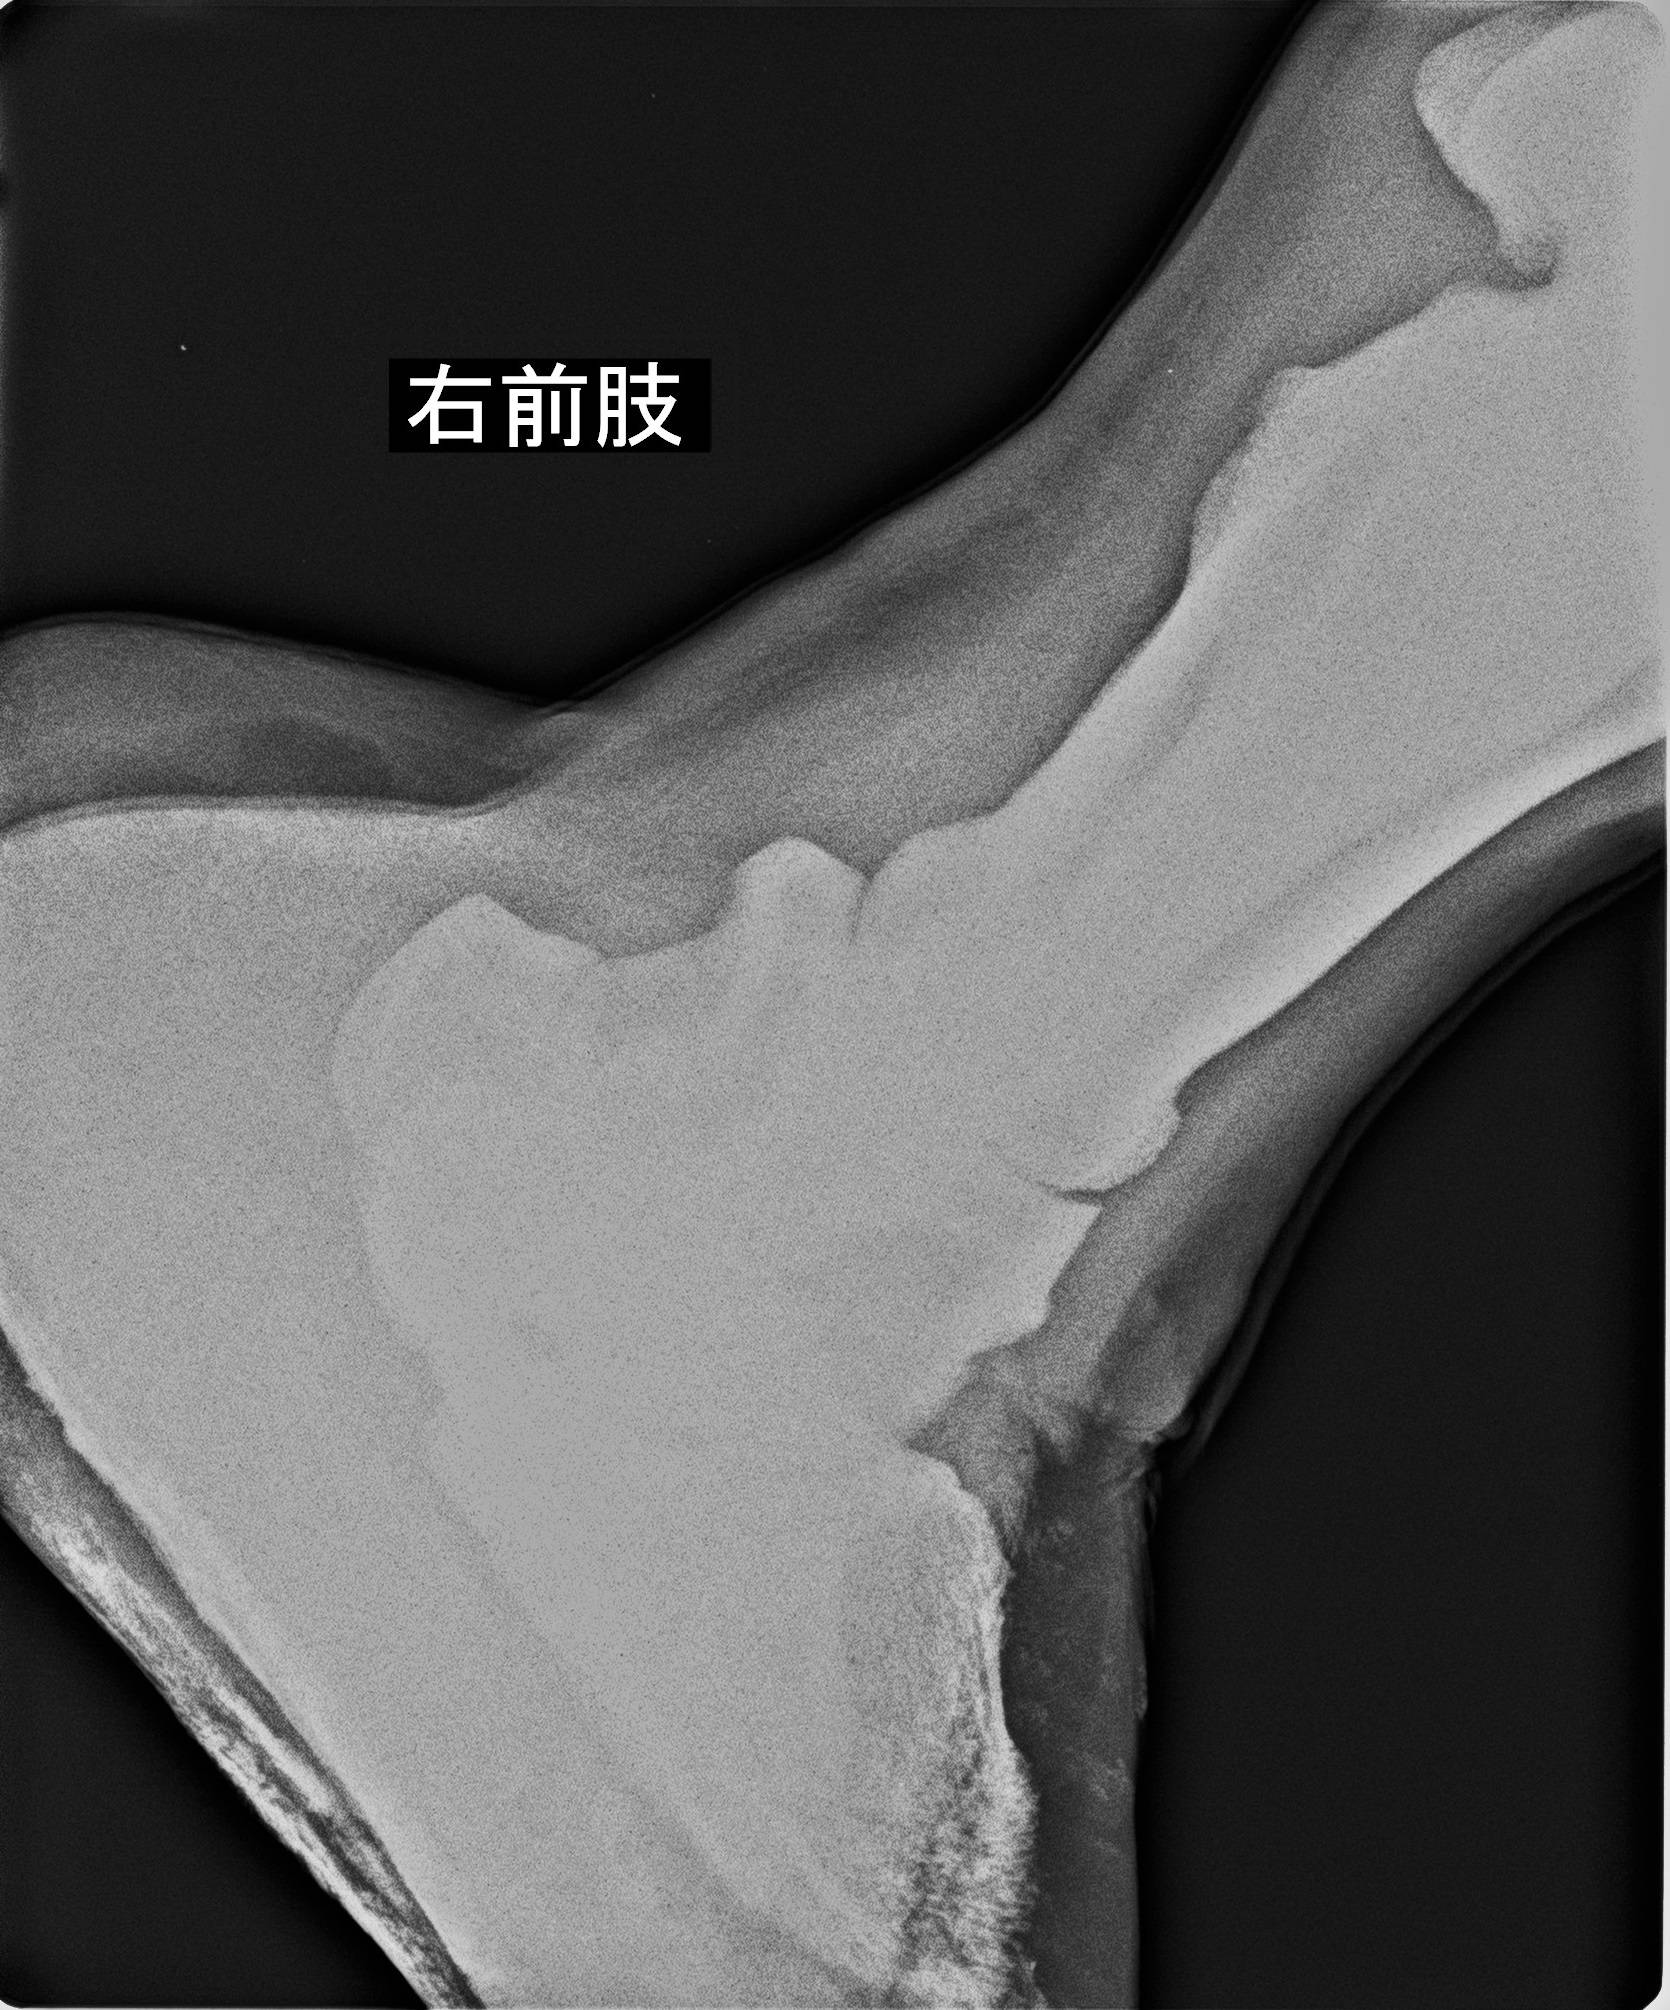

(「そら」の右前肢の一部です。大きいため一枚には収まらないため数回に分けて撮影します)

そして、近年はレントゲン撮影のトレーニングを行い、関節などに異常がないかなども確認しています。

大きなキリンにとっては、蹄は小さいですが、その役割はとても大きく、場合によっては命に係わってきます。だからこそ、注意深く観察し、何かあった時にできる選択肢を増やしていければと思っています。